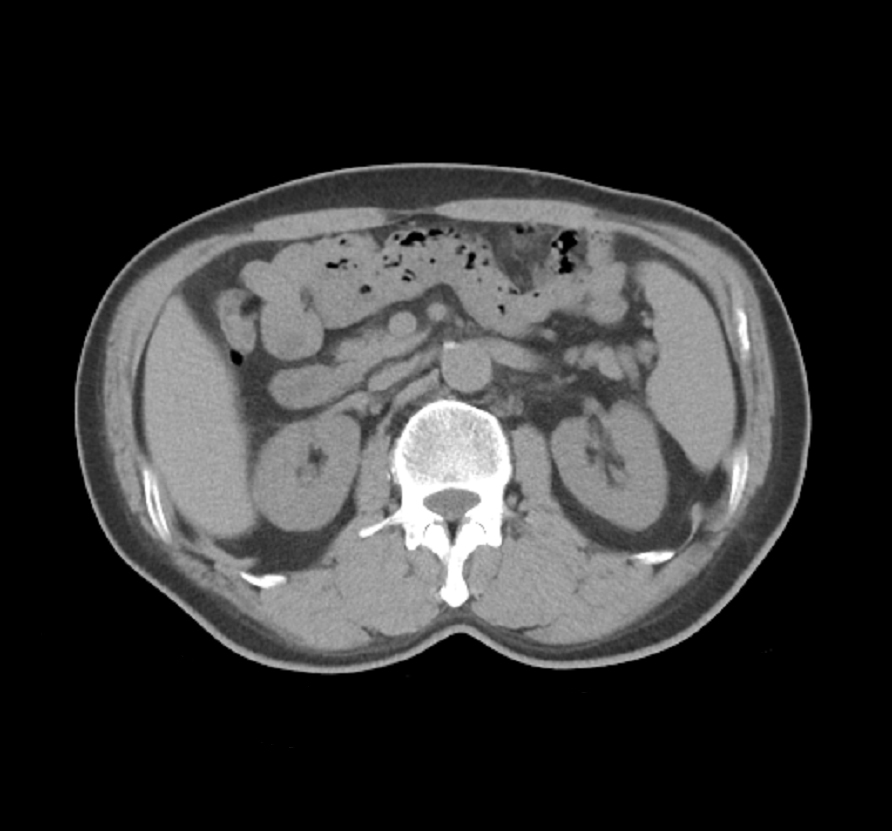

고드프리 하운스필드는 1919년 잉글랜드에서 태어나, 영국 공군에서 전자공학을 배운 후 EMI 사에서 유도무기 및 레이더 연구를 했다. 그는 컴퓨터에 관심을 갖게 되었고, CT 스캐너 개발에 착수하여 1971년 뇌 낭종 환자를 대상으로 최초의 CT 스캔을 성공적으로 실시했으며, 1975년에는 전신 스캐너를 개발했다. 그의 업적은 X선 발견 이후 인체 스캔 진단 기술 발전에 크게 기여했으며, CT 값의 단위인 Hounsfield Number(HU)에 그의 이름이 사용되고 있다. 하운스필드는 1979년 앨런 코르맥과 함께 노벨 생리학·의학상을 수상했다.

시골로 나들이를 갔을 때, 하운즈필드는 물체 주위의 모든 각도에서 X선 촬영을 함으로써 상자 안에 무엇이 있는지 알아낼 수 있다는 아이디어를 떠올렸다. 그런 다음 그는 여러 각도에서 X선으로부터 입력을 받아 "슬라이스"로 물체의 이미지를 생성할 수 있는 컴퓨터를 제작하기 시작했다. 이 아이디어를 의학 분야에 적용하여 현재 계산 단층 촬영으로 알려진 기술을 제안했다. 하운즈필드는 프로토타입 머리 스캐너를 만들어 먼저 보존된 인간 뇌를 대상으로, 다음 정육점에서 구입한 신선한 소 뇌를 대상으로, 그리고 나중에는 자신을 대상으로 테스트했다. 1971년 10월 1일, 영국 런던 윔블던의 앳킨슨몰리병원에서 뇌 낭종 환자를 대상으로 성공적인 스캔을 실시하며 CT 스캐닝이 의료 현장에 도입되었다.[15] 1975년, 하운즈필드는 전신 스캐너를 만들었다. 그는 1975년 전신 스캐너를 도입하는 등 CT 스캔 기술을 계속 개선했으며, 1984년 은퇴 후에도 연구소의 수석 연구원(그리고 컨설턴트)으로 활동했다. 하운즈필드가 개발한 계산 단층 촬영의 원리는 오늘날(2022년)까지도 사용되고 있다.

시골로 나들이를 갔을 때, 하운스필드는 물체 주위의 모든 각도에서 X선 촬영을 함으로써 상자 안에 무엇이 있는지 알아낼 수 있다는 아이디어를 떠올렸다. 그런 다음 그는 여러 각도에서 X선으로부터 입력을 받아 "슬라이스"로 물체의 이미지를 생성할 수 있는 컴퓨터를 제작하기 시작했다. 이 아이디어를 의학 분야에 적용하여 현재 계산 단층 촬영으로 알려진 기술을 제안했다. 당시 하운스필드는 앨런 코맥이 이러한 장치에 대한 이론적 수학에 대해 수행했던 연구를 알지 못했다. 하운스필드는 프로토타입 머리 스캐너를 만들어 먼저 보존된 인간 뇌를 대상으로, 다음 정육점에서 구입한 신선한 소 뇌를 대상으로, 그리고 나중에는 자신을 대상으로 테스트했다. 1971년 10월 1일, 영국 런던 윔블던의 앳킨슨몰리병원에서 뇌 낭종 환자를 대상으로 성공적인 스캔을 실시하며 CT 스캐닝이 의료 현장에 도입되었다.[15] 1975년, 하운스필드는 전신 스캐너를 만들었다. 하운스필드가 개발한 컴퓨터 단층 촬영의 원리는 오늘날(2022년)까지도 사용되고 있다.

1963년과 1964년에 앨런 코르막의 CT 연구 이론 발표를 바탕으로, 영국 EMI사에서 동료들과 함께 뇌를 컴퓨터를 이용하여 디지털 처리하고 단층 촬영하는 장치를 개발했다. 소의 뇌와 하운스필드 자신의 뇌를 촬영한 후, 1971년에 런던의 아킨슨-몰리 병원에서 낭종 환자의 뇌를 촬영하여, 이듬해 1972년에 발표했다. 1975년에는 전신 스캐너 장치를 개발했다. 이 장치는 현재의 CT 장치의 원형이며, 이 발명은 X선 발견 이래 최대의 발명이 되어, 인체의 스캔 진단 기술을 비약적으로 발전시켰다.

하운스필드의 이름은 현재의 CT 값의 단위로 Hounsfield Number 또는 Hounsfield Unit(HF 또는 HU)로 사용되며, 이 값은 -1000HU를 공기, 0HU를 물로 한 흡수율의 상대값으로 정의되어 있다.

1963년과 1964년에 앨런 코르막의 CT 연구 이론 발표를 바탕으로,[23] 영국 EMI사에서 동료들과 함께 뇌를 컴퓨터를 이용하여 디지털 처리하고 단층 촬영하는 장치를 개발했다.[23] 소의 뇌와 하운즈필드 자신의 뇌를 촬영한 후, 1971년에 런던의 아킨슨-몰리 병원에서 낭종 환자의 뇌를 촬영하여, 이듬해 1972년에 발표했다.[23] 1975년에는 전신 스캐너 장치를 개발했다.[23] 이 장치는 현재의 CT 장치의 원형이며, 이 발명은 X선 발견 이래 최대의 발명이 되어, 인체의 스캔 진단 기술을 비약적으로 발전시켰다.[23] 같은 해 왕립학회 회원으로 선출되었다.[23]

하운즈필드의 이름은 현재의 CT 값의 단위로 Hounsfield Number 또는 Hounsfield Unit(HF 또는 HU)로 사용되며,[23] 이 값은 -1000HU를 공기, 0HU를 물로 한 흡수율의 상대값으로 정의되어 있다.[23] +1000 HU를 뼈로 하는 설명을 자주 보지만, 이것은 잘못이다.[23]